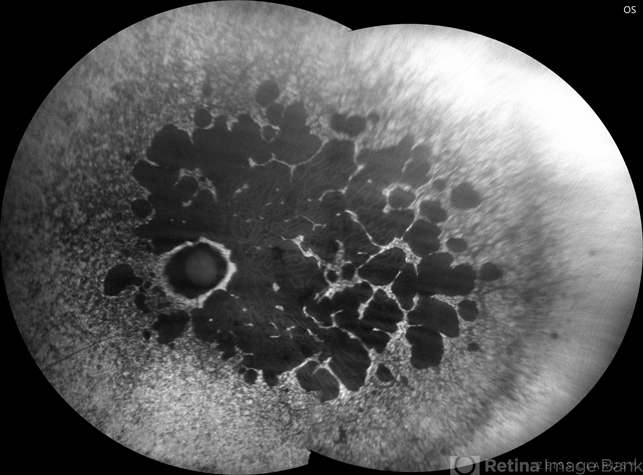

- hereditary retinal degeneration, hereditary retinal dystrophy, rod cone dystrophy

- Fundus autofluorescence of the left eye in a 58 yo male with rod cone dystrophy. He presented with night blindness and peripheral vision loss since youth and recent decrease in central vision for the past 10 years. Notice multiple coin shaped hypoautofluorescent pacthes within central 20 degrees which are coalescing centrally. (fundus photo uploaded separately) He has one pathogenic variants of both CEP290 and PRPH2 genes.